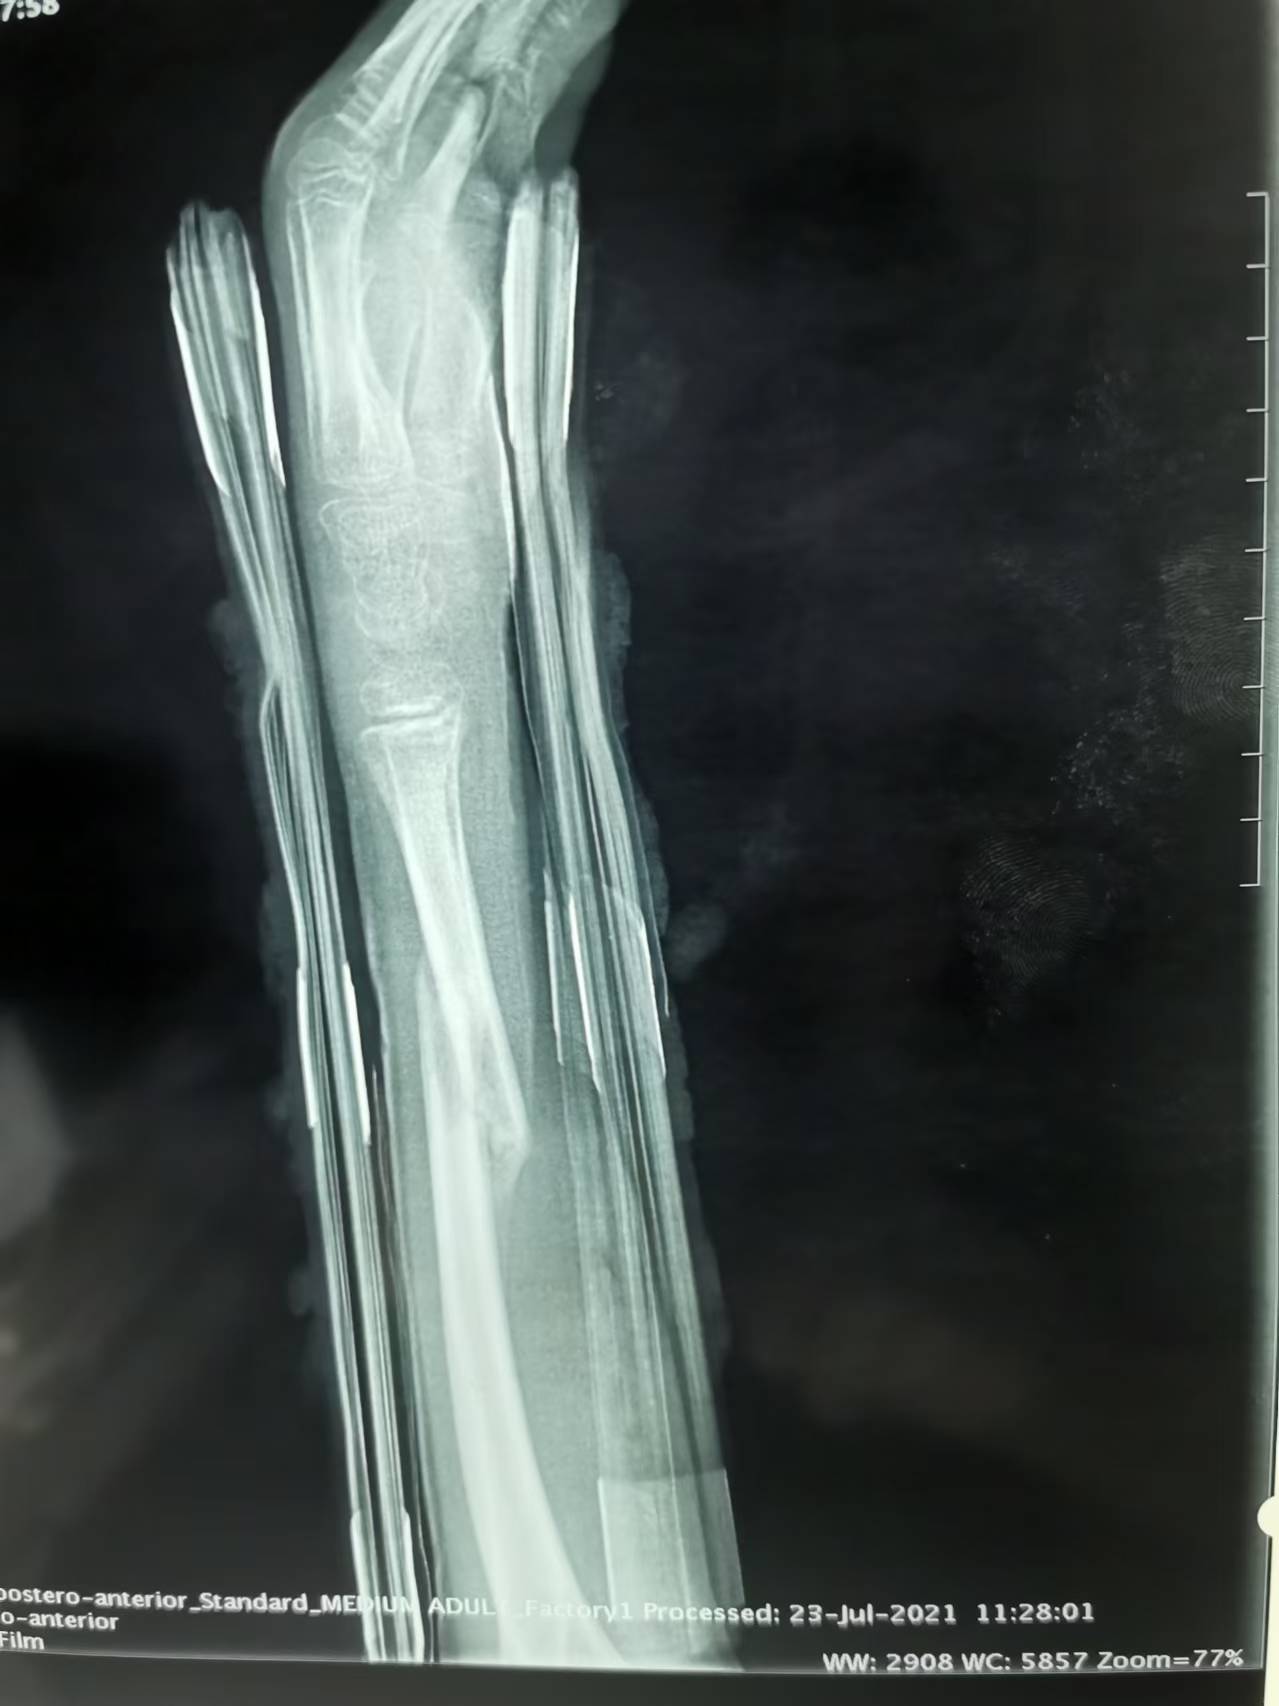

首页 > 张恒云工作室 > 影像资料 三